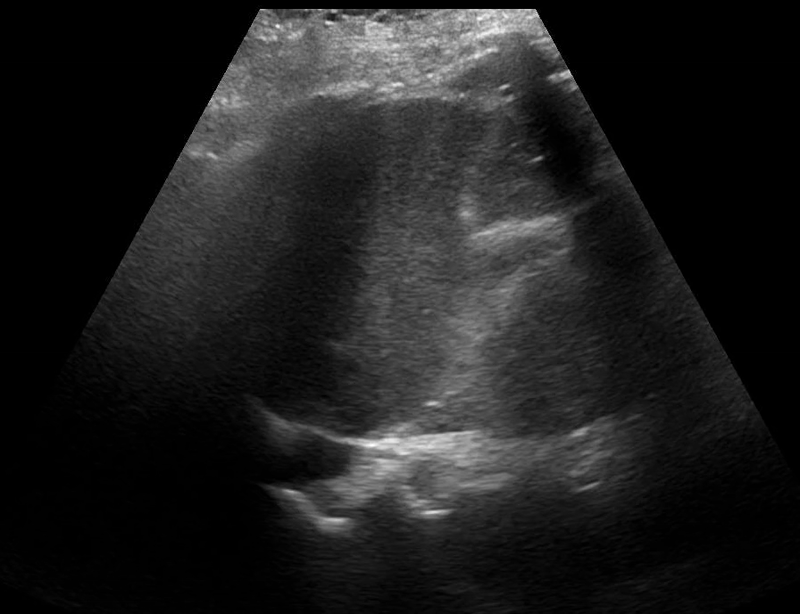

Image 3: POCUS thoracic of the right hemidiaphragm with a negative ‘spine sign.’